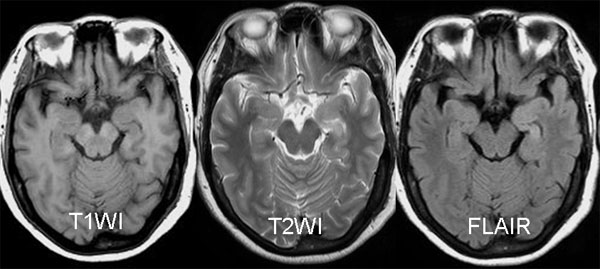

以下是引用三博在2009-9-10 12:42:00的发言:[br]病理:左侧海马硬化。[br]苍白球软化灶。[br]左侧海马信号增高,体积变小,右侧海马信号未见明显异常,